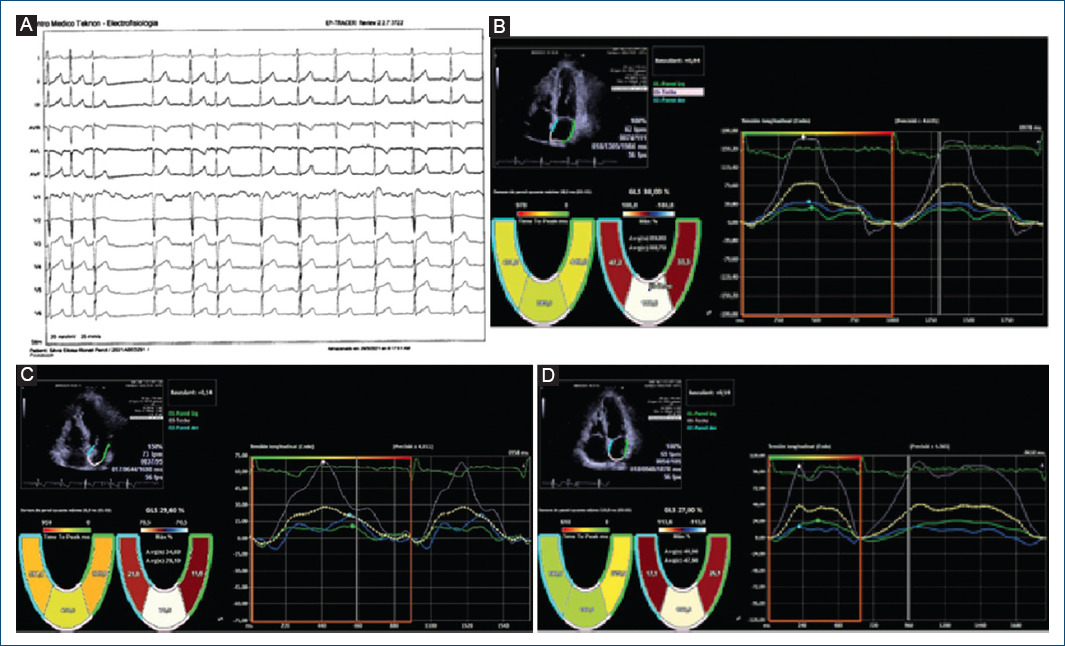

Intriguingly, in our study, we observed in a non-protocolized way some models of basal dyssynchrony and dynamic image sequences after an atrial extra systole that suggest different pathogenesis at the beginning of repetitive forms. Figure 1 suggest the origin of extra systole at the level of the pulmonary veins whose arrhythmogenic potential is classically defined and in addition, there is an anatomical alteration in intratrial conduction involving in some way the Bachmann’s fasciculus. This patient presented atrial fibrillation just before the ablation, during catheter manipulation and showed RUNs, and PAF in the follow-up Holters not seen in the initial analysis. Figure 2 show the initial sequences of extra systoles with changes in longitudinal and segmentary strain that guide on the functional state of the left atrium and its adaptation mechanisms.

Figure 1 Global and segmental atrial strain with “gating” in the electrocardiograph R wave. Correlative frames that include an atrial extra systole and the different behavior of its longitudinal segmental deformation curves that suggest different points of origin of the arrhythmia and probably different pathogenesis. 55-Year-old female patient with elevated blood pressure treated with Angiotensin Converting Enzyme inhibitors, family history of ablated atrial fibrillation and atrial extra systole of moderate density, that was documented for the last two years not showing repetitive forms (control group) with clinical limitation to effort without obvious structural heart disease. The basal electrocardiogram showed no alterations to the P wave and the and the extrasystole was positive on the lower side and V1 with negativity in a VL suggestive of an origin in the posterior left superior pulmonary vein. (A) The basal echocardiogram showed no significant alterations or signs of delay in electro-mechanical activation or asynchrony. (B) shows the deformation curves of the septal, posterior and lateral walls during sinus rhythm, showing a maximum peak of positive longitudinal elongation. very predominant posterior aspect with slight asynchrony as regards the activation of the septal and lateral walls (18 ms) with reservoir strain values within normal ranges. During extra systole (C) we saw a decrease in global and segmental strain values with a reduction in the activation time of the posterior wall and a significant increase in asynchrony with respect to the septal and lateral walls. This suggests anisotropic conditions and a type of left intra-atrial block with delay in the activity of the basal segments possibly involving the Bachmann’s fascicle. In (D) we observe beats after the extra systole with a tendency to recover the initial global and segmental strain values.